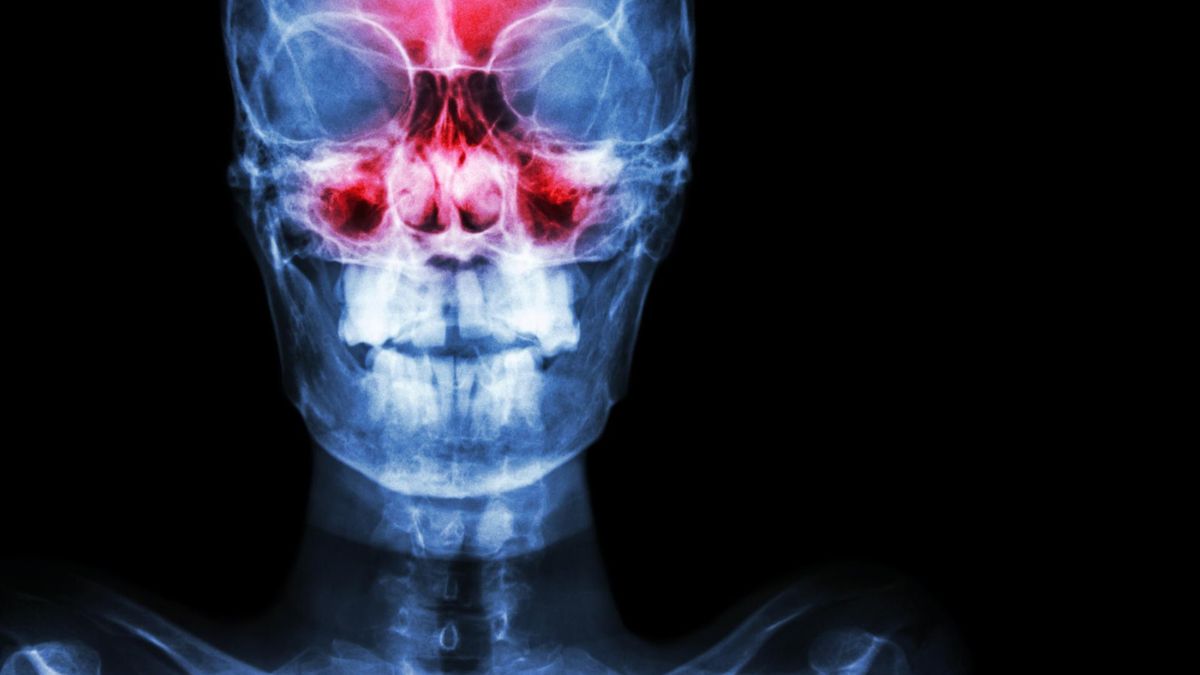

Pojawia się przy pochylaniu lub intensywnym wysiłku. Ból zatok, który zwiastuje infekcję. Z pewnością wielu z nas nie raz męczyło się z uczuciem rozpierania między oczami, u szczytu nosa. Większość z nas wie więc, jak trudno pozbyć się choroby, która nieleczona, powraca ze zdwojoną siłą.

Jeśli nie chcesz po raz kolejny łykać tabletek, wypróbuj równie skuteczne, a naturalne sposoby na infekcje zatok. Stosuj je za każdym razem, gdy poczujesz, że twoje zatoki znów zaczynają się zatykać.